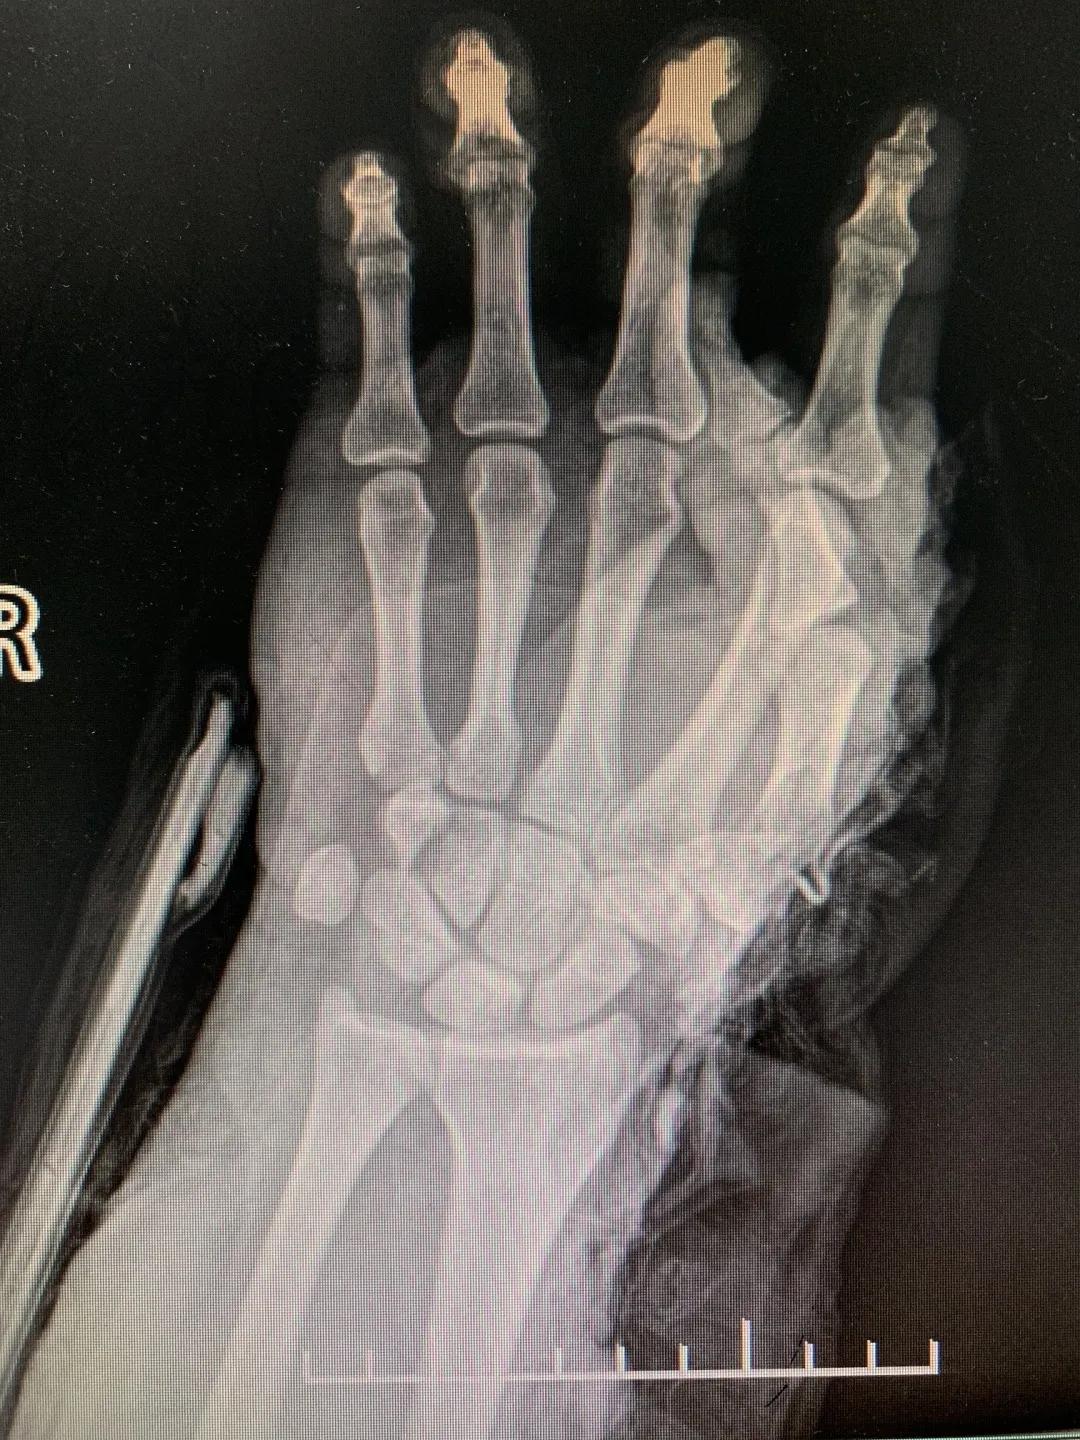

“正常的肢体都有皮肤保护着,如果没有皮肤,我们的肌肉、血管、神经、骨骼露在外面,都会发生坏死。”苑芳昌介绍,伤者的情况非常复杂,伴有多发骨折、肱骨骨折、骨关节的多发错位,还有腕部的骨折,更有血管、神经损伤。不仅如此,伤者右臂在机器里面受到绞伤,肌肉也已经大面积挫伤,各种复杂情形交织在一起甚至让手术“无从下手”。